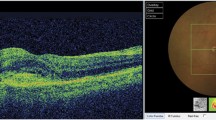

Because our purpose was to identify CNV, we included all types of CNV in the CNV population and all types of macular disease in others. In Fig. 1 is an example of imaging obtained for CSCR (no CNV) and in Fig. 2 an example of images presented for a patient with type 2 CNV.

Patient#1 presenting a typical case of CSCR on FA and SD-OCT Imaging. Yellow arrow serous detachment of the neurosensory retina in the macula area in FA. White arrow appearance of a single dot of fluorescein with leakage over the course of the angiogram. Star subretinal hyporeflective area on SD-OCT imaging: retina serous detachment. Yellow bracket thickened choroid